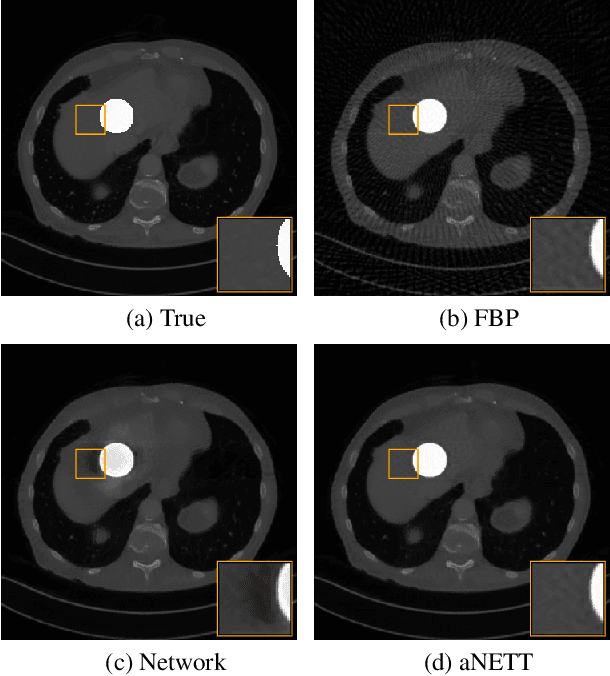

Abstract:We propose a sparse reconstruction framework (aNETT) for solving inverse problems. Opposed to existing sparse reconstruction techniques that are based on linear sparsifying transforms, we train an autoencoder network $D \circ E$ with $E$ acting as a nonlinear sparsifying transform and minimize a Tikhonov functional with learned regularizer formed by the $\ell^q$-norm of the encoder coefficients and a penalty for the distance to the data manifold. We propose a strategy for training an autoencoder based on a sample set of the underlying image class such that the autoencoder is independent of the forward operator and is subsequently adapted to the specific forward model. Numerical results are presented for sparse view CT, which clearly demonstrate the feasibility, robustness and the improved generalization capability and stability of aNETT over post-processing networks.